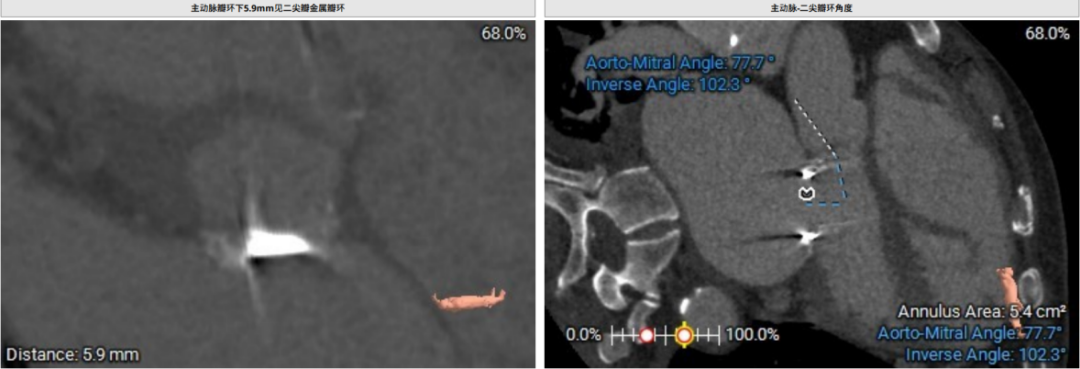

术前CT评估示:患者二尖瓣生物瓣置换术后,原生物瓣型号未知,生物瓣金属环平均内径25.9mm,外径31.5mm,瓣架高度15.9mm;

主动脉-二尖瓣角度:102.3°;

术中建议造影角度:RAO 58°/CRA 44°;RAO 49°/CRA 62°。